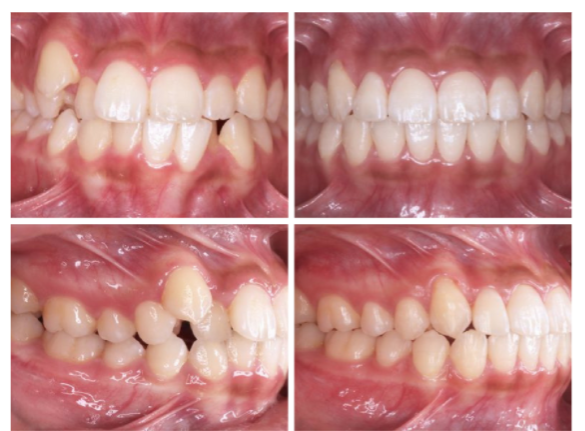

这个牙挺乱的吧,虎牙突出,拥挤,深覆合,过咬合,这个是很多小伙伴都有的问题。看看看,这个case你们觉得够复杂吗?Invisalign做到了,45个牙套,64周,16个月完成啦!